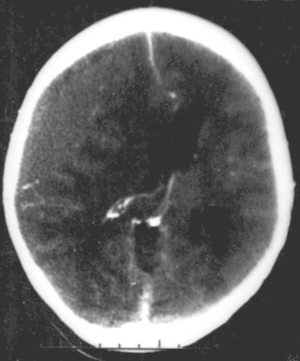

Brain trauma in the developing human is a common cause (over 400,000 injuries per year in the US alone, without clear information as to how many produce developmental sequellae)[32] of neurodevelopmental syndromes. It may be subdivided into two major categories, congenital injury (including injury resulting from otherwise uncomplicated premature birth)[2] and injury occurring in infancy or childhood. Common causes of congenital injury are asphyxia (obstruction of the trachea), hypoxia (lack of oxygen to the brain) and the mechanical trauma of the birth process itself.